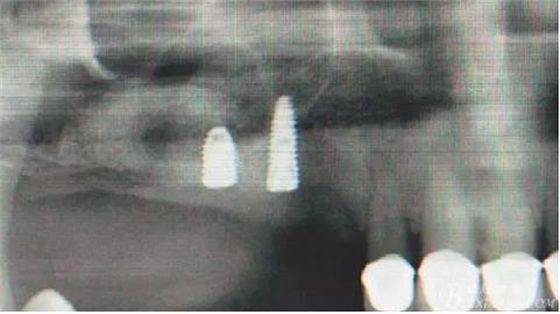

14,15牙位植入兩顆植體,6,7牙位骨高度嚴(yán)重不足,且骨密度低,無(wú)法給植體提供良好的初期穩(wěn)定性,需二期植入。13牙位骨寬度不足,沒有植骨、植植體,修復(fù)時(shí)用后面4顆連冠加一顆3的游離臂是沒有問(wèn)題的。當(dāng)然這里我們不去討論這個(gè)方法的合理性,我們今天的話題是改良式外提升技術(shù)的應(yīng)用。

術(shù)后X光片。

術(shù)后40天X光片。